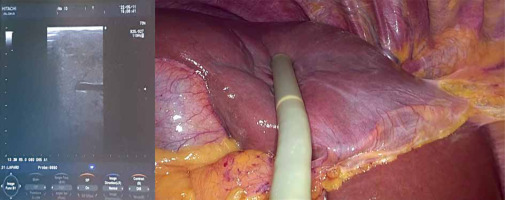

Intraoperative ultrasound (Photo 2), with its low cost and high availability, is a necessary tool for every surgeon performing LLS due to its high sensitivity and ability to moderate the lack of haptic feedback during parenchyma examination [11]. It can assess the precise location of the tumor and its anatomic relations and helps plan intraoperatively transection lines avoiding unexpected collision with large hepatic vessels. Therefore, using intraoperative ultrasound is recommended by numerous authors [12, 13]. Indocyanine green (ICG) fluorescence imaging-guided LLS is a less common technique that uses the mechanism of binding of ICG to plasma proteins excreted only by the liver, but not by the lesion. ICG may be administered preoperatively, most commonly 10 days before the scheduled operation, to better identify the tumor, which preserves the dye, whilst normal liver parenchyma washes it out during that time. ICG can also be given intraoperatively to help identify the intersegmental planes of the liver, which is beneficial in performing anatomical resection, but this technique requires vast experience in LLS [14]. ICG is becoming a more common technique and, according to recent data, may lead to lower blood loss (BL) and postoperative complications. However, more multi-center prospective studies are needed [15].